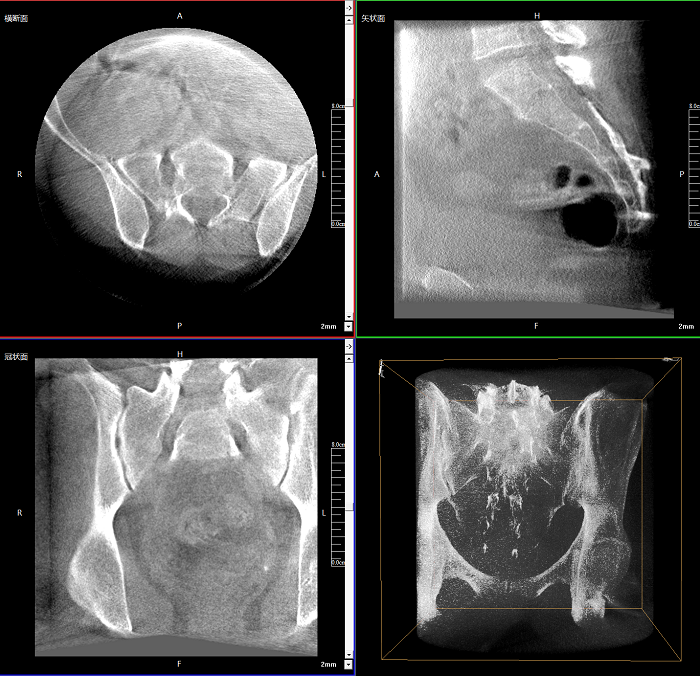

三維成像 全面觀察

任意視角、任意切面觀察

術中實時生成橫斷面、矢狀面、冠狀面及三維影像,可在任意切面、任意角度評估植入物和解剖結構的相對位置。

術中CT檢查 減少翻修概率

通過術中三維影像的檢查,可以立即發(fā)現(xiàn)植入物的錯位,減少不必要的第二次手術,減少并發(fā)癥概率以及感染風險。

400萬像素成像

易于觀察細微病灶,利于胸部、腹部、脊柱關節(jié)等復雜骨骼和軟組織的成像。

Clinical picture

臨床圖片